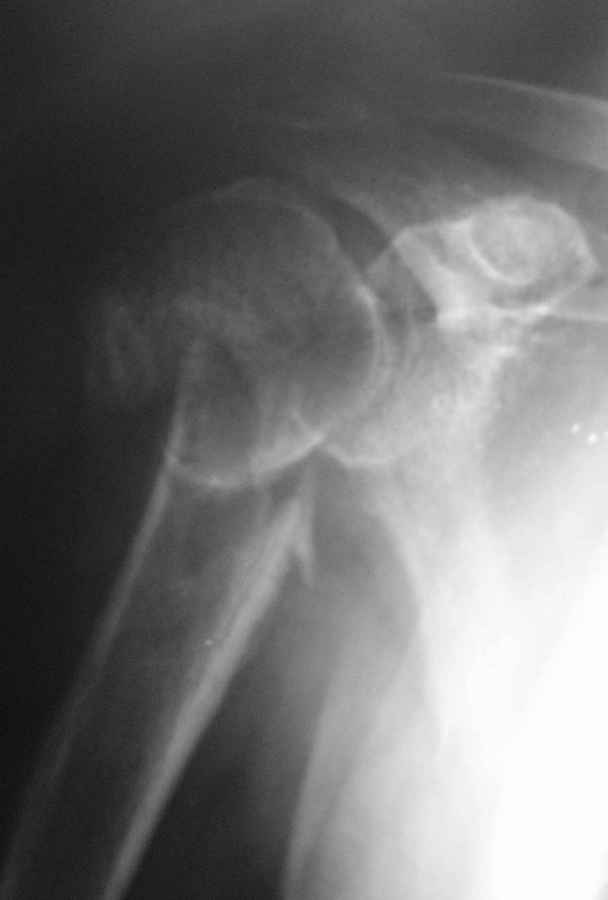

Пациент 55 лет. травма 7.07.09г (первая Р-грамма). Лечился консервативно, надолго выпадал

из под наблюдения леч. врача. Последний снимок от 7.08.09г.как видно на Р-грамме стояние

отломков неудовлетворительное, клинически выраженная патологическая подвижность. Соп.

дз: сахарный диабет 1 типа, средней тяжести. Выскажите Ваше мнение о дальнейше тактике

лечения данного пациента.